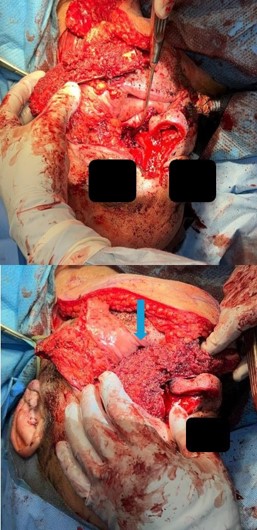

The procedure began with a left Weber-Ferguson incision. The visible abnormal skin was marked out and removed. This involved 70% of the nasal dorsum extending from the rhinion to the cephalic aspect of the lower lateral cartilages and nasal ala. An intraoral left gingival labial sulcus incision was made extending to the midline of the soft palate and laterally to the gingivobuccal sulcus. The periosteum was elevated with a periosteal elevator, and a reciprocating saw was used to make bony cuts. These were performed through the right lateral nasal bone, junction part between the right maxilla and right nasal bone, and extending into the lower piriform aperture. Another bony cut was made horizontally between the nasal bone and frontal bone superiorly. This was extended to the left medial canthus to include the left orbital medial orbital wall rim and left orbital floor. Lastly, the saw was used along the left anterior maxilla with the intention of removing the maxillary sinus wall completely. Intraoperatively, the tumor was noted to extend into the left parapharyngeal space. Dissection was carried out, staying outside the palpable primary tumor while leaving a sleeve of healthy margin. The bony cuts were then used to cut through the hard palate on the left side and posteriorly separated from the soft palate. No bone cuts were made along the left nasal wall to ensure an en bloc resection. Soft tissue structures were then dissected freely. With the nasal cavity exposed, the saw was used to cut through the hole in the nasal septum. There were multiple defects present, including a skin defect around 6×4 cm, a mucosal defect of 3×4 cm, a left midface defect of 8×6 cm, and a hard palate defect of 6×4 cm. Margins were then carefully obtained and showed no residual tumor. A left modified neck dissection was then performed, and vessels were located for microvascular anastomosis.

A chimeric scapular free flap was chosen for reconstruction because it provides multiple bony components and skin for reconstruction. A 10×2.5 cm segment of the lateral border of the scapula and entire scapular tip was harvested along with the subscapular muscle. The skin paddle obtained was parascapular. The two components of the flap were noted to have two separate arterial origins but shared venous drainage. The flap was then placed into the defect of the face. The bony aspect of the flap was utilized to reconstruct the hard palate and maxillary defect with osteotomies (Figure 3). Proximal scapular bone was plated to the residual hard palate and distal portion to the anterior maxillary process. Two nasal trumpets were placed through bilateral nasal vestibules. The middle portion of the skin paddle was de-epithelialized and used to pack into the nasal cavity. Medpor supported the left orbital contents and was secured to the scapular tip. The scapular tip was affixed to the left zygoma and frontal bone with a reconstruction plate. Then, titanium mesh was used for the nasal bony defect, and the skin paddle’s distal end covered it entirely (Figure 4). The microvascular anastomosis was then performed, drains and nasogastric tube were placed, and incisions were closed. The patient was admitted to the intensive care unit, where hourly flap perfusion checks were performed using a Cook arterial monitoring probe. The patient followed an uncomplicated post-operative course, with discharge on the seventh day.

The patient was seen in an outpatient setting for a two week follow-up and discussion of final pathology results. These showed two masses: ameloblastoma with the invasion of the hard palate, posterior maxilla, and maxillary sinus (Figure 5) as well as a SCC with the cartilaginous and bony invasion of the nasal septum and nasal bone (Figure 6). During this clinic visit, he reported some discharge from one of the incisions and flap edema. He was otherwise doing well, with significant improvements in dysphagia and nasal obstruction. The flap adhered well to native tissue and appeared healthy. The infection cleared up over the next two weeks on a course of antibiotics, and the patient’s nasogastric tube was removed within the following three weeks.